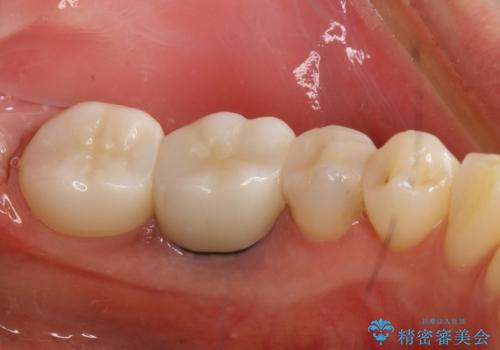

左下5はセラミックインレー修復、左下6,7はオールセラミッククラウンにて修復していくこととしました。

見た目、使用感ともに満足していただきました。現在は他の部位も治療中です。